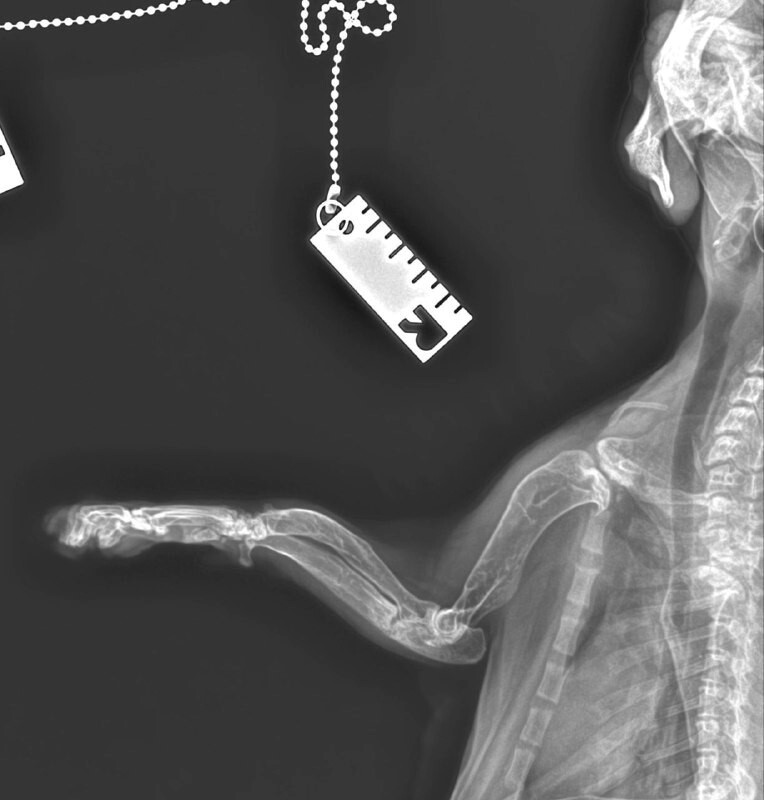

Наш пациент – кастрированный кот по кличке Порш, метис, изначально поступил в ноябре 2025 года на прием ортопеда-травматолога. У кота с рождения наблюдалась деформация костей скелета, хромота, непропорциональное укорочение конечностей, карликовость. Кроме того, владелицу беспокоило. Что кот малоподвижный, не активный, и большую часть времени – лежит в своей лежанке. Коту провели ортопедический осмотр и выполнили несколько рентгеновских снимков.

Наш ортопед-травматолог выделил основные изменения - признаки эпифизарной дискинезии (недоразвитие эпифизов длинных костей), укорочение тел позвонков в грудном отделе и задержка закрытия эпифизов.